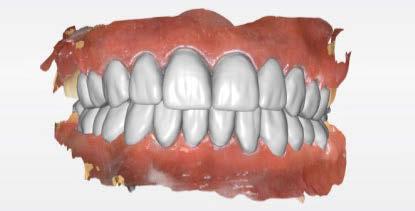

dentarias, cumpliendo parámetros biológicos, terapéuticos, mecánicos y estéticos. Después se realizó un modelado digital retrospectivo (Figuras 7-11) para generar modelos impresos 3D para realizar el mock up funcional, estético y como guía para las preparaciones (Figuras 12-15). Con ello, se efectuaron las preparaciones dentarias y los registros intermaxilares y, posteriormente, se digitalizaron ambos maxilares (Figuras 16-21)

Terminada esta fase se elaboró una propuesta de diseño (CEREC,

SW 5.2, Dentsply Sirona) (Figuras 22-27), la cual fue materializada en dos tipos de materiales a partir de bloques cerámicos IPS Empress CAD y cerámica vítrea de disilicato de litio IPS E.max CAD (Figuras 28-30)